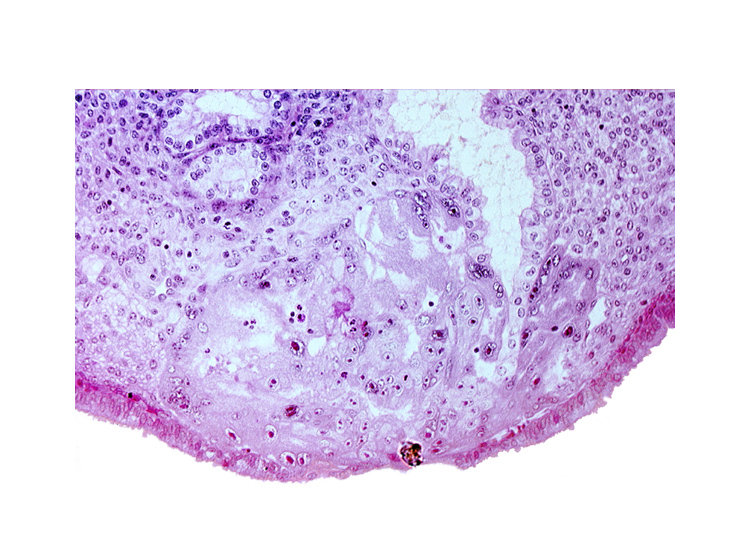

Carnegie Embryo #8004 | Location: 11-05-03

Keywords: disrupted endometrial epithelium, lumen of endometrial gland, maternal blood cells in lacunae, syncytiotrophoblast, syncytiotrophoblast engulfing endometrial gland cells

Source: The Virtual Human Embryo.